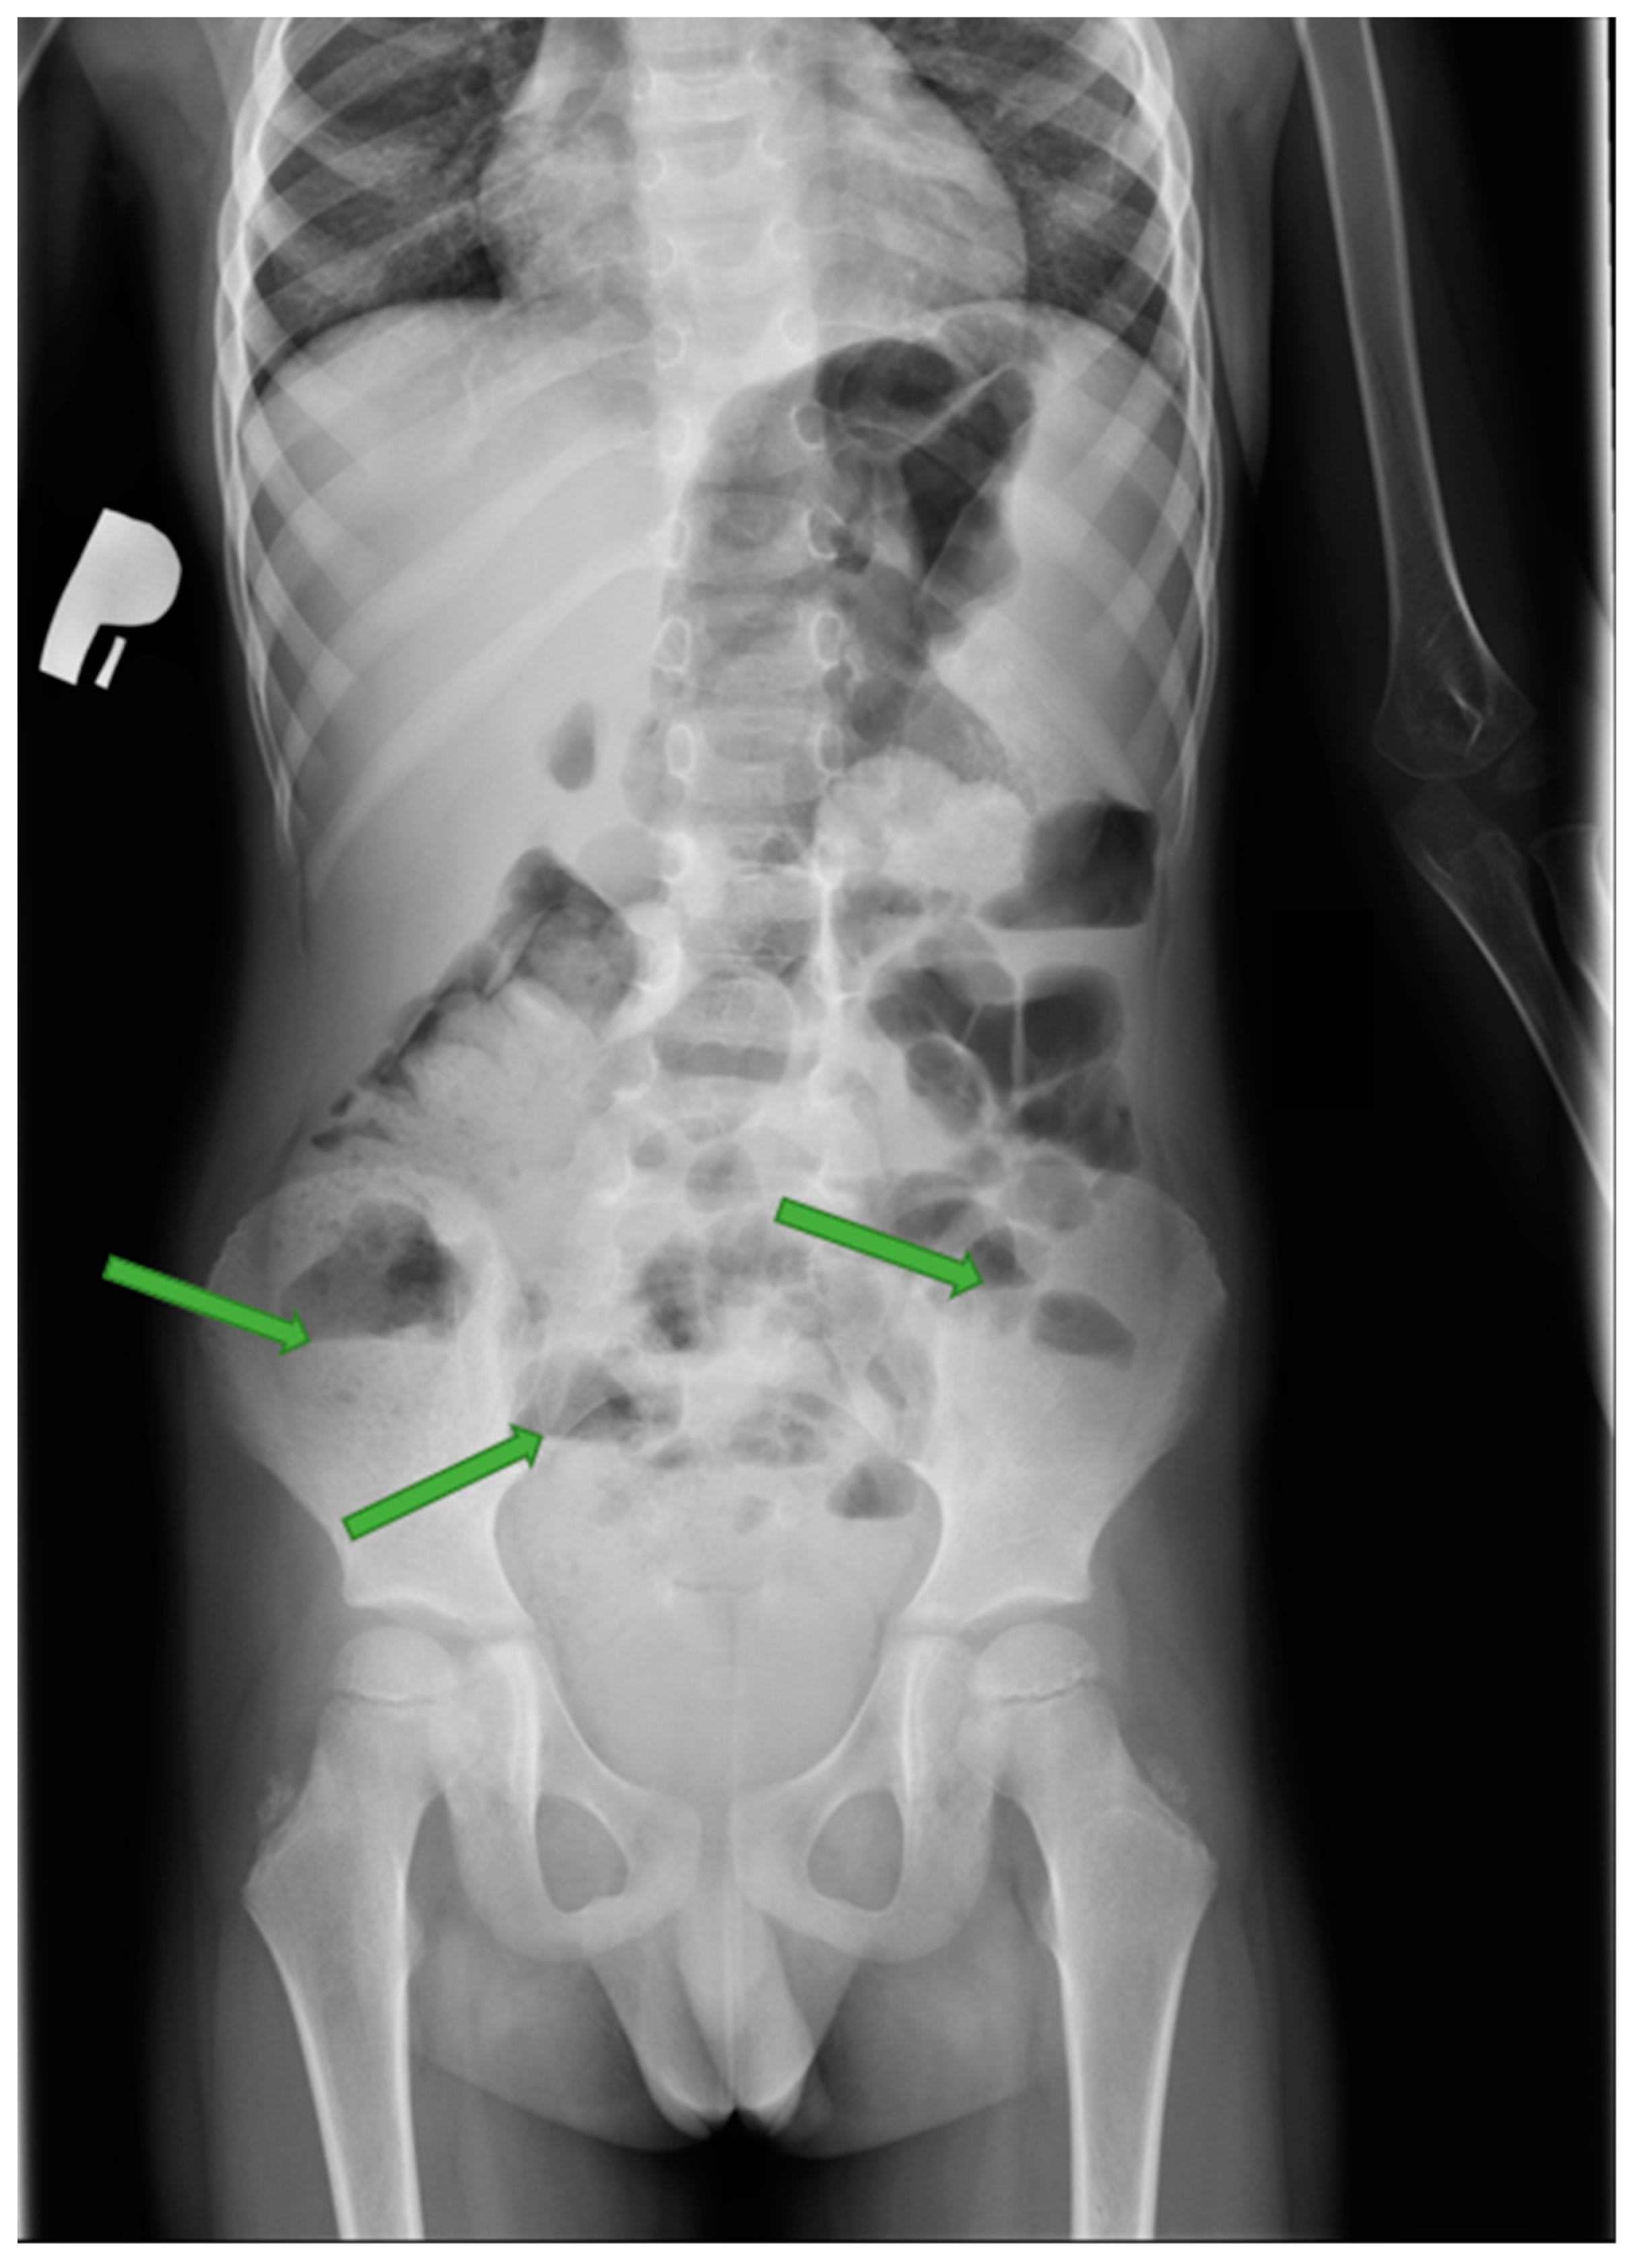

4. Case Presentation